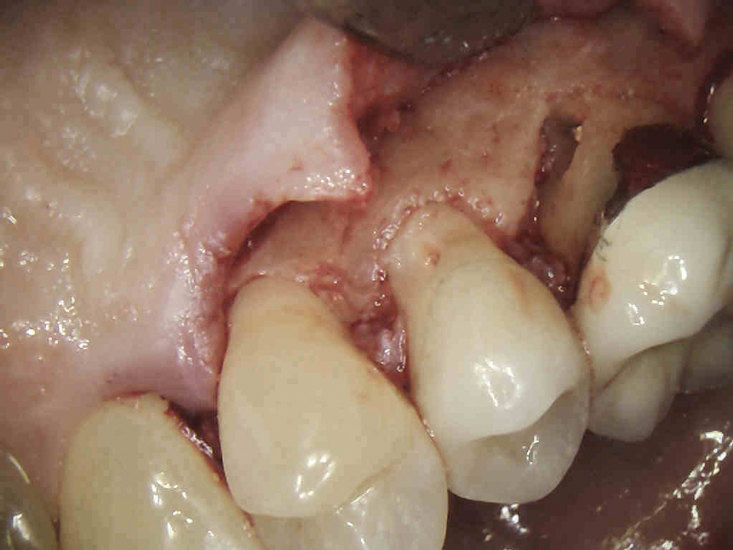

(4.) The granulation tissue was removed in its entirety, and the defects were treated with a 90% TCA solution.

Figure 4

(5.) The defects were filled with a bioactive, biocompatible calcium silicate-based restorative cement.

Figure 5

Once prepared, the resorptive cavity should be treated topically with a 90% trichloroacetic acid (TCA) solution. TCA serves to eliminate any remaining clastic cells, which are known to tunnel through the dentin beyond the visible cavity margins.5 Because TCA is quite caustic, to avoid injury, care must be taken to prevent it from accidentally being applied to the bone or soft tissue.8 Place a small amount of TCA in a small glass dappen dish and apply it to the resorptive lesion with a large absorbent paper point or small cotton pellet.5 TCA causes coagulation necrosis of any residual resorption tissue; however, this effect is nonspecific, so it is crucial to apply it carefully because it can cause chemical burns to the oral mucosa or skin.8

After TCA treatment, the resorptive cavity should be restored with a biocompatible restorative material that does not wash out in saliva or gingival crevicular fluid. Due to this latter requirement, resin-modified glass ionomers are often more appropriate restorative materials in these cases than other bioceramic materials.8,9 Once restored, the patient should be recalled for follow-up appointments at 6 months and at 1 year postoperatively, at a minimum, to assess the progress of healing and for any recurrent resorption.5